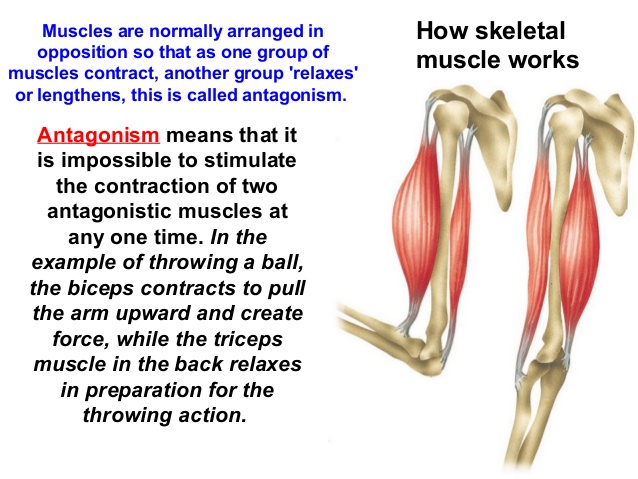

3. Antagonistic Muscles:

These are so called because when one of them contracts, the other relaxes at the same time to bring about the desired movement e.g. bicep muscle and tricep muscle in the forelimb.

Movement at the elbow is controlled by two antagonistic muscles, the bicep muscle and the tricep muscle.

To lift the lower forelimb, the bicep muscle contracts and the tricep muscle relaxes. To lower forelimb, the bicep muscle relaxes while the tricep muscle contracts.

3. Antagonistic Muscles:

These are so called because when one of them contracts, the other relaxes at the same time to bring about the desired movement e.g. bicep muscle and tricep muscle in the forelimb.

Movement at the elbow is controlled by two antagonistic muscles, the bicep muscle and the tricep muscle.

To lift the lower forelimb, the bicep muscle contracts and the tricep muscle relaxes. To lower forelimb, the bicep muscle relaxes while the tricep muscle contracts.